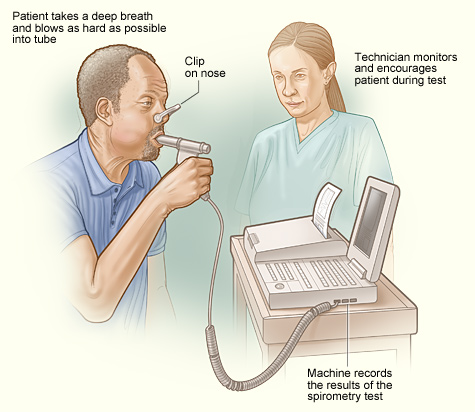

2 – Diagnostic Tools – Spirometry, Arterial Blood gas, Oximeter, Exercise Tolerance Testing, X-ray, Bronchoscopy, Culture and Sensitivity Tests, Sneezing Reflex, Coughing Reflex,